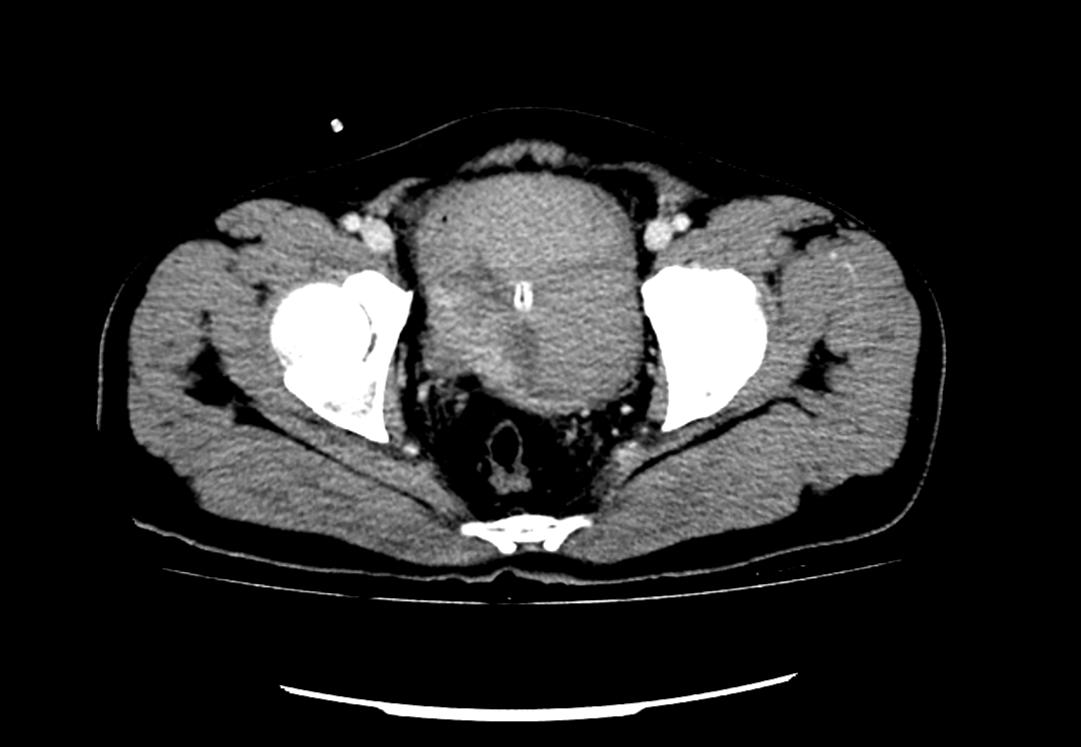

患者為53歲的男性,患者因肉眼血尿就診我院門診,行泌尿系CT考慮膀胱占位,建議患者住院治療,入院后完善膀胱MRI檢查進(jìn)一步診斷膀胱腫瘤,侵犯肌層。行膀胱腫物激光切除后,病理學(xué)檢查明確“膀胱高級(jí)別尿路上皮癌,肌層浸潤(rùn)”診斷,結(jié)合泌尿外科診療指南建議行根治性膀胱全切術(shù)。

泌尿外科醫(yī)生團(tuán)隊(duì)術(shù)前將患者情況上報(bào)醫(yī)務(wù)科,并組織了多次會(huì)診?;颊?/span>“肌層浸潤(rùn)性膀胱癌”診斷明確,術(shù)前完善心肺功能排除無(wú)明顯手術(shù)禁忌,結(jié)合指南推薦及泌尿外科團(tuán)隊(duì)成員綜合意見(jiàn),決定在全麻下行腹腔鏡下膀胱根治性切除+盆腔淋巴節(jié)清掃+回腸代膀胱手術(shù)。術(shù)前嚴(yán)格完善準(zhǔn)備工作,手術(shù)歷經(jīng)7小時(shí),完整切除了患者的膀胱、前列腺及精囊,并行回腸代膀胱。手術(shù)順利,術(shù)后3天可正常行走,復(fù)查患者各項(xiàng)指標(biāo)正常。